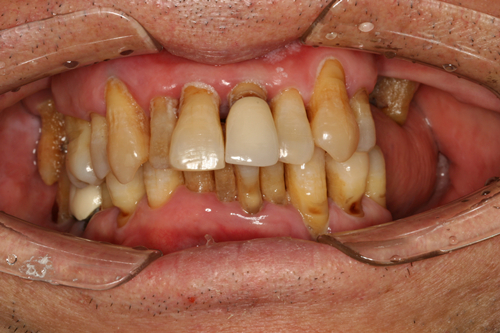

随着年纪的增大,性格开朗、生活无忧的郭老也开始为牙齿健康所犯愁,原来在十几年前,郭老就已经安装假牙,但当时技术、条件并不好,假牙用过几年后就脱落了,在后期的检查过程中还查出口腔患有晚期牙周炎,经过拔牙、治疗后,仍然没有达到满意的效果,治疗后的牙冠让他吃东西塞牙、吃东西无味,让他苦不堪言。

在经过多地走访后,慎重的郭老最终选择了麦芽口腔,郭老曾表示:“选对口腔机构很重要,选对一名优秀的、技术好的、负责任的口腔的医生更为重要,我相信麦芽口腔,相信郑院长的经验和技术。”

通过一系列的检查后,麦芽口腔郑苍尚院长为他量身定制了“微创无痛数字化口腔种植牙”技术,舒适的种牙体验,就像被蚊子“叮”了一下牙就种好了,用郭老的话说:“种牙过程很轻松,全程无痛,种完后也不肿不痛的,相信麦芽就是相信科学。”

如今缺牙多年的人民日报社老记者郭灵声,终于又“长”出一口漂亮的牙齿!